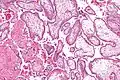

- Micrograph showing chorionic villi. Intermediate magnification. H&E stain.

Chorionic villi are villi that sprout from the chorion to provide maximal contact area with maternal blood.

They are an essential element in pregnancy from a histomorphologic perspective, and are, by definition, a product of conception. Branches of the umbilical arteries carry embryonic blood to the villi. After circulating through the capillaries of the villi, blood returns to the embryo through the umbilical vein. Thus, villi are part of the border between maternal and fetal blood during pregnancy.

The bulk of the villi consist of connective tissues that contain blood vessels. Most of the cells in the connective tissue core of the villi are fibroblasts. Macrophages known as Hofbauer cells are also present.